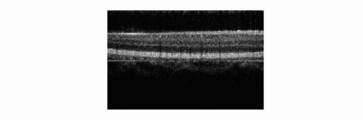

• Fig. 4A shows an OCT image according to the first embodiment.

• Fig. 4B shows the OCT image according to the first embodiment.

• Fig. 4C shows the OCT image according to the first embodiment.

• Fig. 4D shows an OCT image when an optical filter is not provided.

• signal processing including a Fourrier transformation processing operation is performed on the basis of data of the measurement, three OCT images are obtained as shown in Fig. 4.

• the interference signals, which influence the crosstalk are converted into OCT images, as shown in Fig. 4D, an unclear image that is superimposed by a portion of another beam image as a noise component is formed.

• OCT images formed by a plurality of beams, are such that measuring signals for forming tomographic images having reduced noise components can be obtained at a high speed with a sensor array having a minimum number of pixels.